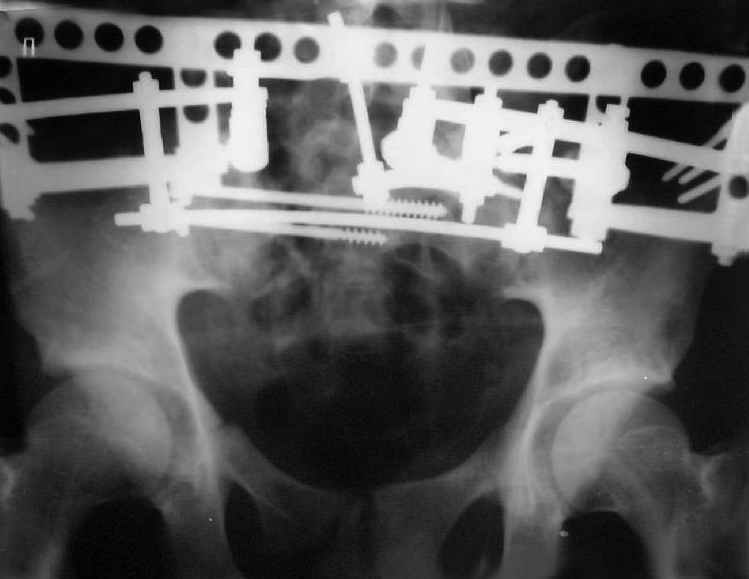

Re: Застарелый перелом таза

Для информации к размышлению о возможности исправления имеющейся деформации предлагаю похожий случай.